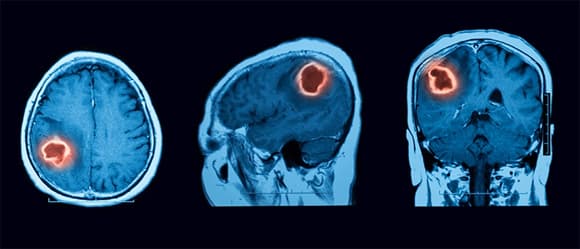

Theo các bác sĩ Khoa Ngoại Thần kinh, Bệnh viện K (Hà Nội), u não là tình trạng các tế bào trong não phát triển mất kiểm soát, tạo thành khối u bất thường. Các khối u này có thể khởi phát từ tế bào não, tế bào đệm của hệ thần kinh trung ương hoặc bắt đầu từ các bộ phận khác như phổi, thận… di căn lên não.

U não bao gồm hai loại: lành tính và ác tính. Khối u ác ở não rất dễ tấn công và di căn sang các vùng tế bào khỏe mạnh lân cận. Bệnh phát triển nhanh, dễ tái phát và ảnh hưởng trực tiếp đến tính mạng bệnh nhân. Theo thống kê, tỷ lệ sống sót sau 5 năm đối với người bệnh u não ác tính chỉ từ 10 tới 33%.

Các dấu hiệu và triệu chứng của khối u não phụ thuộc vào kích thước và vị trí của khối u não. Các triệu chứng cũng có thể phụ thuộc vào tốc độ phát triển của khối u não, còn được gọi là cấp độ khối u.